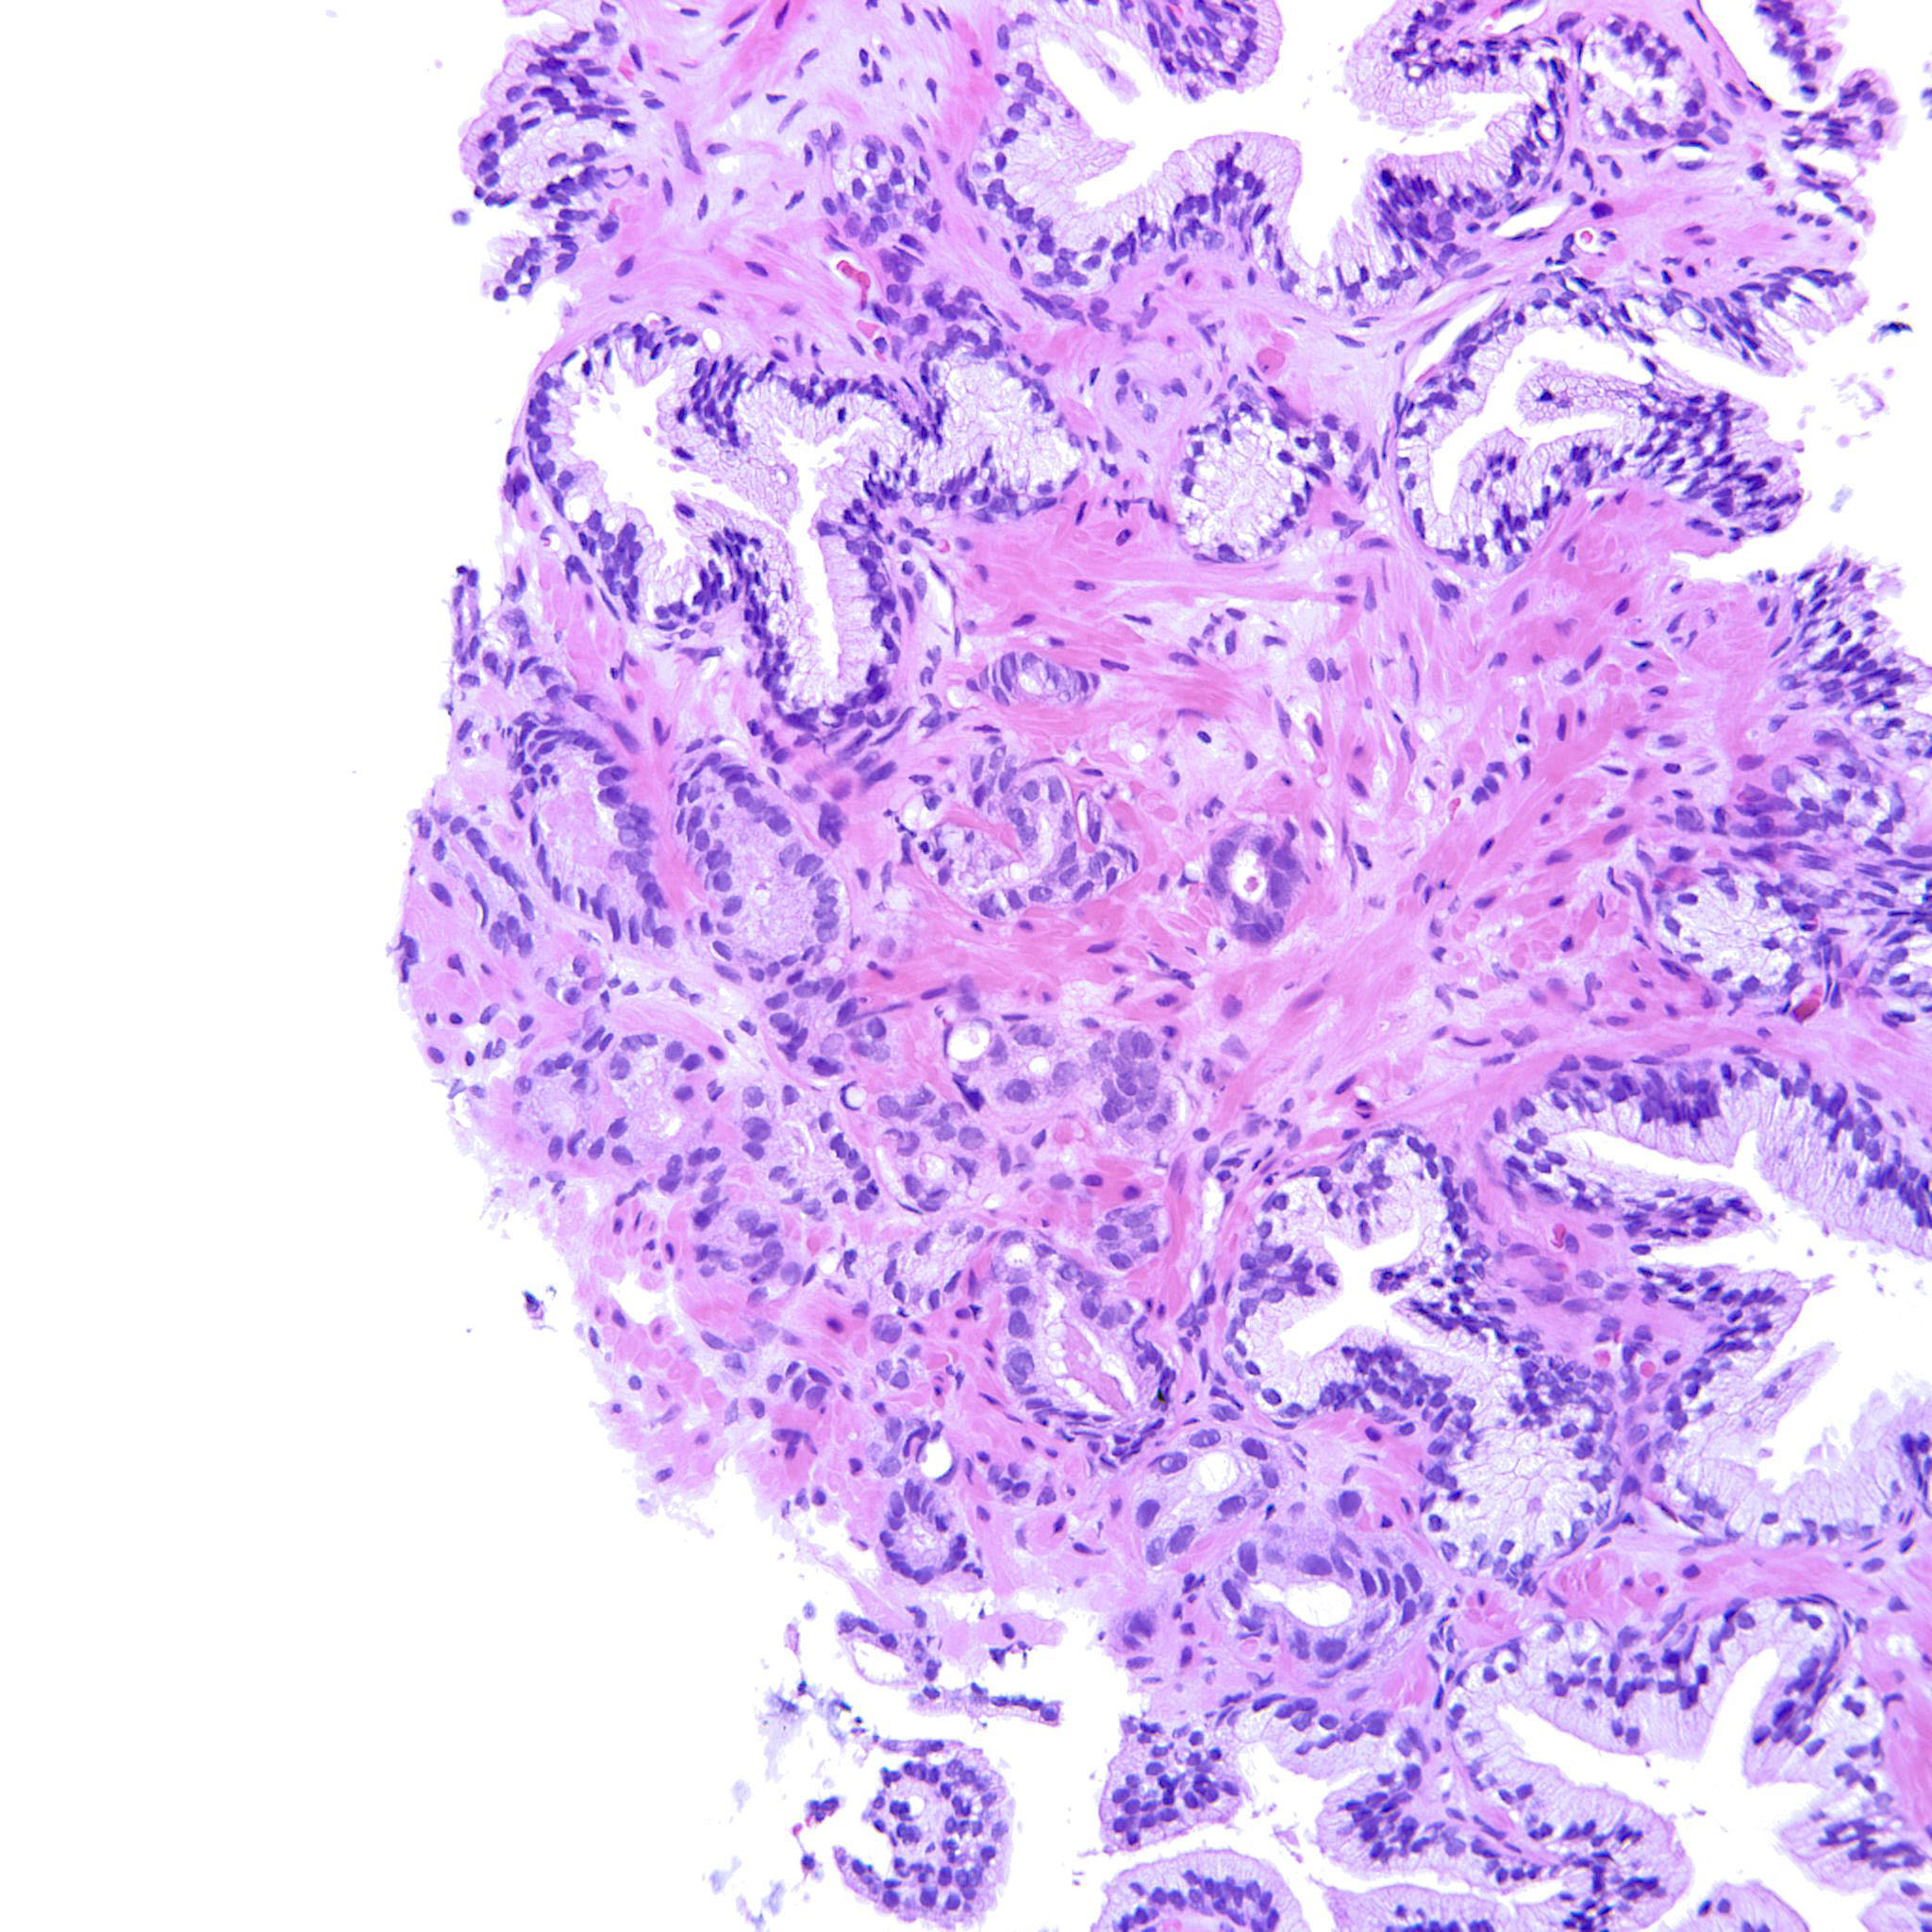

Prostate cancer grading

Case ID: 207